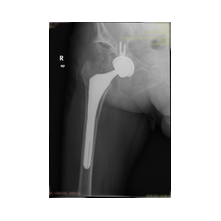

Peki kalça protezi ameliyatın da neler yapıyoruz? Diz protezi ameliyatındaki benzer aşamaları uyguluyoruz. Kalça eklemi dize göre yapısal olarak ve çalışma sistemi olarak farklıdır. Kalça eklemi bir yuva ve onun içinde hareket eden femur başı dediğimiz bir toptan oluşur. Kalça eklemi kireçlenmesinde bu baş ve yuva yüzeyindeki kıkırdakların aşınması sonucu başın yuvarlaklığı kaybolur, sonuçta ağrı ve hareket kısıtlılığı ortaya çıkar. Bu yüzeyleri değiştirirken öncelikle bu başı kesip atıyoruz. Daha sonra yuvayı yine kılavuzlarla oyup uygun büyüklükteki protezi sıkıştırdıktan sonra en az 2 vida ile kemiğe adapte ediyoruz. Daha sonra alt uyluk kemiğini yine kılavuzlar yardımı ile oyduktan sonra kemiğe adapte ediyoruz ve sistemi birleştiriyoruz.

Görüntüleri büyütmek için üzerine tıklayınız.